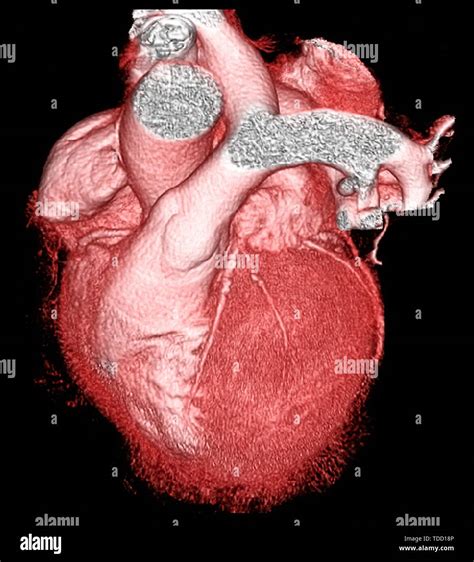

Cardiovascular health remains a top priority for medical professionals and patients alike, especially as diagnostic technology continues to evolve. When doctors need to get a clear, detailed look at the coronary arteries to assess the risk of heart disease, they often turn to advanced imaging techniques. A Ct Scan For Heart, clinically known as a Coronary Computed Tomography Angiography (CCTA) or a Coronary Artery Calcium (CAC) scan, has become a cornerstone in modern preventative cardiology. By providing high-resolution images of the heart's structure and its surrounding blood vessels, this non-invasive procedure allows physicians to identify potential blockages or calcification long before a patient experiences a major cardiac event.

The primary purpose of a Ct Scan For Heart is to evaluate the health of the coronary arteries. These vessels are responsible for supplying oxygen-rich blood to the heart muscle. Over time, these arteries can accumulate plaque—a buildup of fat, cholesterol, calcium, and other substances. If left unchecked, this plaque can harden or rupture, leading to restricted blood flow and an increased risk of heart attacks. Unlike traditional stress tests, which measure how the heart functions under pressure, a CT scan provides a direct visualization of the anatomy, allowing for a precise "map" of the arterial state.

• Coronary CT Angiography (CCTA): This scan utilizes an iodine-based contrast dye to highlight the interior of the arteries, allowing radiologists to see not only calcified plaque but also "soft" plaque that could potentially block blood flow.

Once the scan is complete, a specialized radiologist or cardiologist will analyze the hundreds of images produced to identify any narrowing of the arteries or presence of plaque. The results are typically compiled into a report that quantifies the extent of atherosclerosis. If your calcium score is high or significant blockages are found, your doctor will move from a preventative approach to an active management plan. This might include aggressive lipid-lowering therapies (such as statins), lifestyle interventions like specific exercise programs, or further invasive procedures if the blockage is deemed critical.